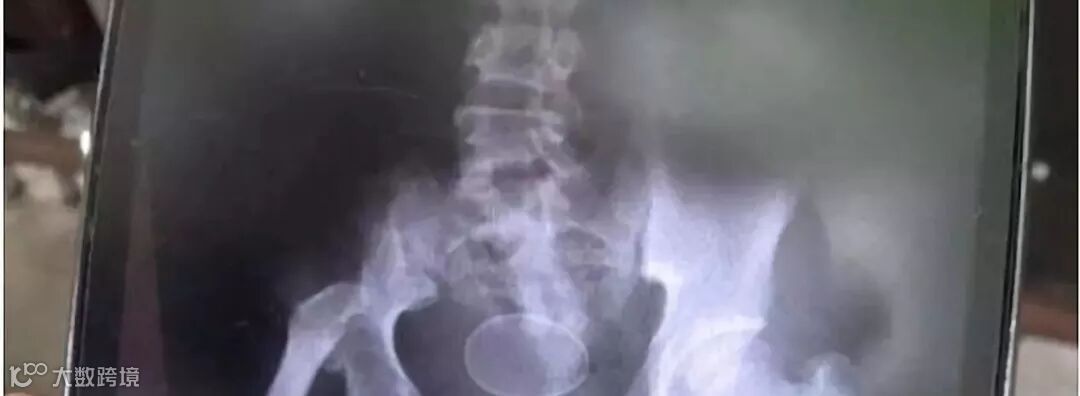

阿克莫身体X光照片